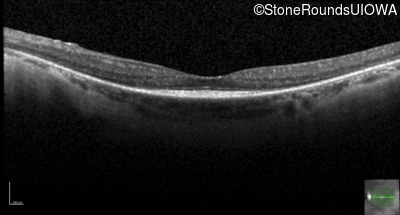

Optical Coherence Tomography - Left - 20/20 -2

Exemplar / OCT Stack